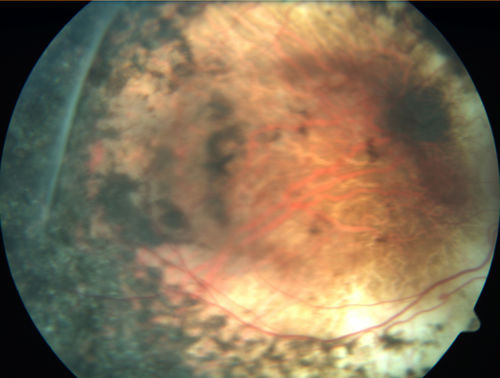

Enhanced S Cone Syndrome - Goldmann Favre - NR2E3 Mutation

82 year old man with poor vision for many years. VA HM OD, 5/200 OS. Diagnosed at age 12 with retinitis pigmentosa. Nystagmus.